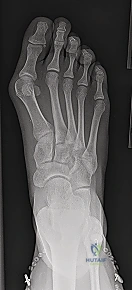

Before we even consider making an incision, our blueprint for this procedure begins with meticulous preoperative planning. We've thoroughly evaluated the patient's weight-bearing anteroposterior (AP) and lateral radiographs of the foot. These images are critical for assessing several key parameters:

- Intermetatarsal Angle (IMA): The primary indication for a Scarf osteotomy is typically a symptomatic hallux valgus with an IMA of less than 20 degrees. We're looking for a stable first metatarsocuneiform joint here; instability might push us towards a fusion.

- Hallux Valgus Angle (HVA): This measures the lateral deviation of the great toe.

- Distal Metatarsal Articular Angle (DMAA): This assesses the orientation of the articular surface of the first metatarsal head. An abnormal DMAA, especially in juvenile hallux valgus, can be corrected effectively with a Scarf.

- Interphalangeal Angle (IPA): If this angle is significantly elevated, it may indicate the need for a concurrent proximal phalangeal osteotomy, such as an Akin osteotomy, to achieve complete correction. We've templated for this possibility.

- Metatarsal Length: We assess for any relative shortening or lengthening that might be required. The Scarf is unique in its ability to allow for shortening, lengthening, rotation, displacement, or even plantarization of the first metatarsal head.

- Joint Congruency: We note the congruency of the first metatarsophalangeal (MTP) joint. While the Scarf is excellent for arthritic hallux valgus not severe enough for a fusion, severe incongruity or advanced arthritis might warrant a different approach.

- Osteophytes: Presence and size of any dorsal or medial osteophytes.

- Medial Eminence: The size of the bony medial eminence, or "bunion," which we will resect.

- Sesamoid Position: The position and condition of the sesamoids under the first metatarsal head. Lateral subluxation is a hallmark of hallux valgus, and their reduction is a key indicator of successful correction.

Today's patient presents with symptomatic hallux valgus, an IMA of 16 degrees, and moderate lateral sesamoid subluxation, making the Scarf osteotomy an ideal choice.